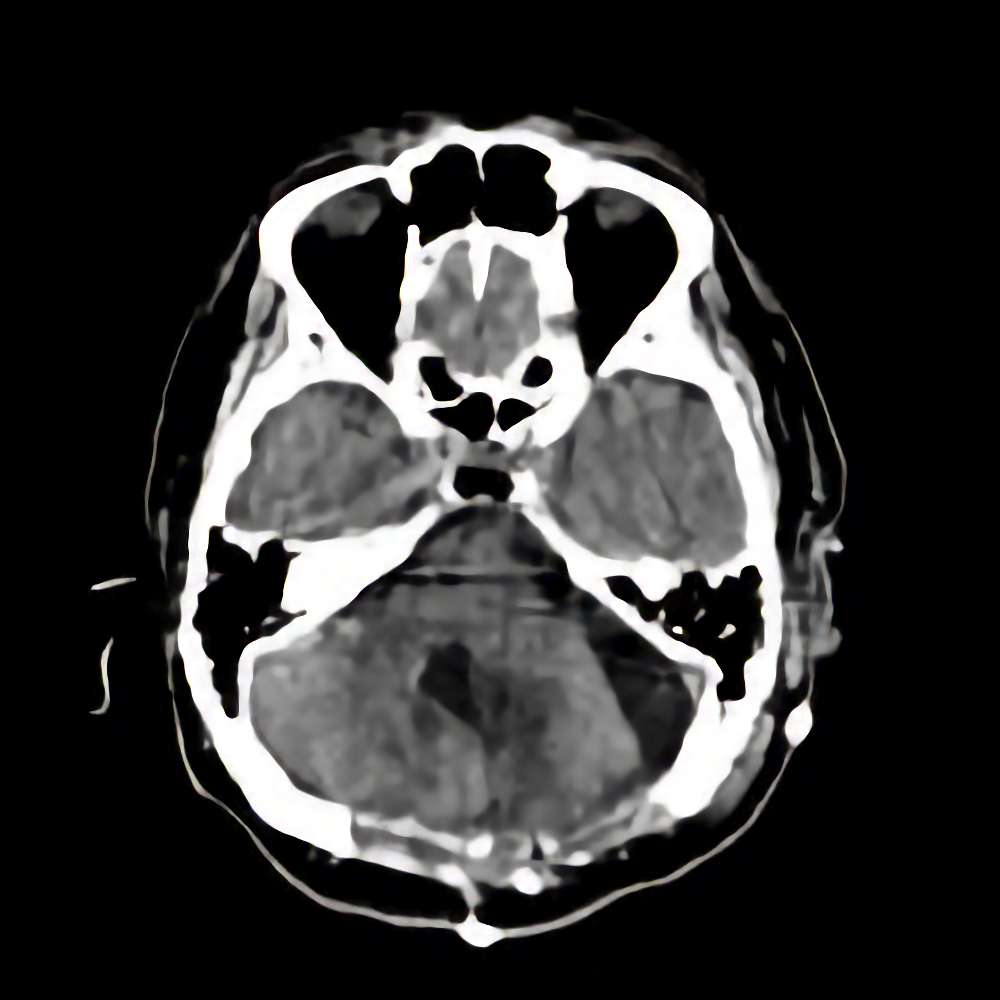

脳腫瘍

断層撮影

手術前1

No.’14_42 手術前1